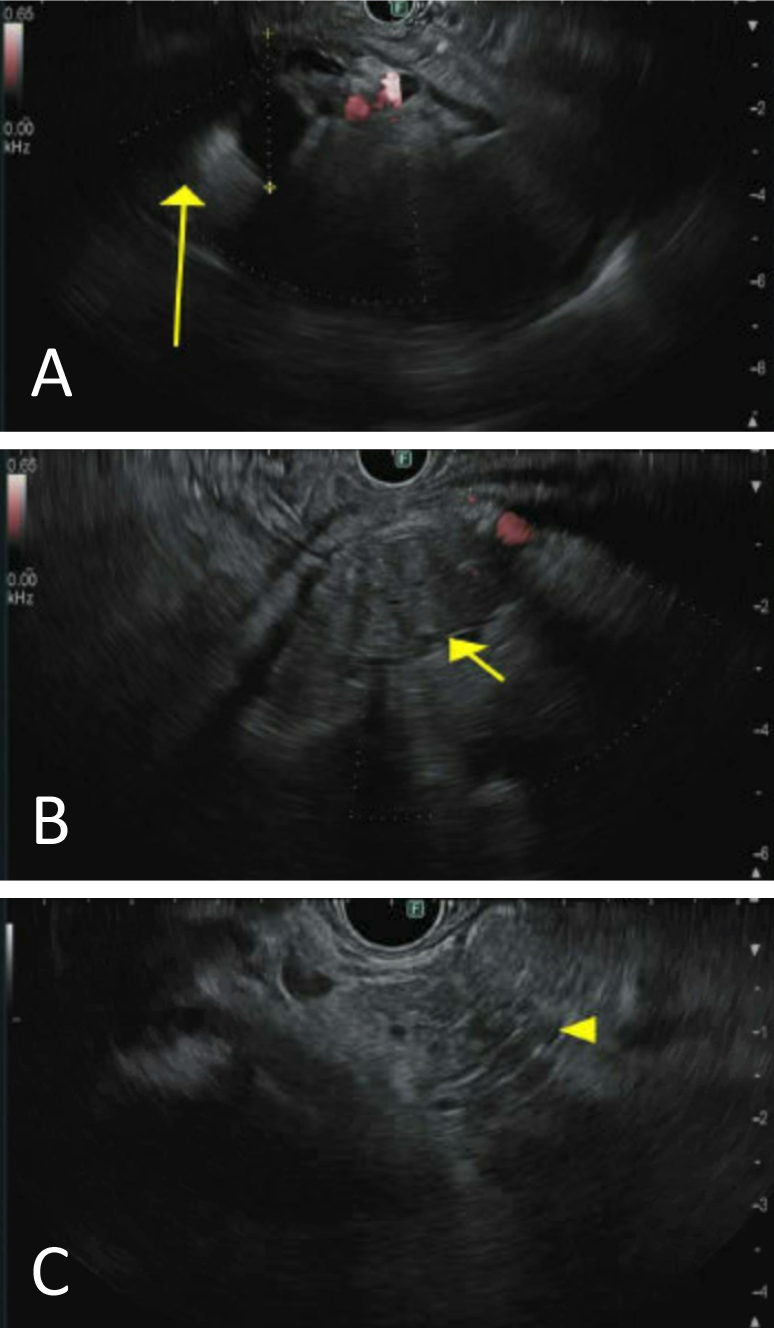

Masses were found in the (A) tail, (B) body, and (C) head of the pancreas.